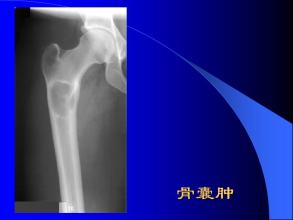

骨囊腫

骨囊腫是骨的瘤樣病變,又名孤立性骨囊腫。囊壁為一層纖維包膜,囊內(nèi)為黃色或褐色液體。主要以手術(shù)治療為主,預(yù)后良好。